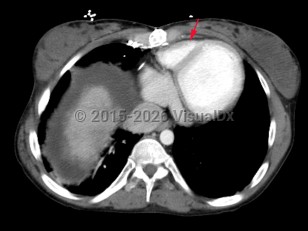

Tricuspid atresia

Congenital lack of tricuspid valve formation resulting in cyanosis and a murmur. An atrial septal defect, hypoplastic right ventricle, and ventricular septal defect are generally present. Other congenital lesions such as transposition of the great arteries may also be present. About half of cases present with cyanosis and a murmur on the day of birth. An additional 30% are diagnosed in the first month. With advances in fetal ultrasound, tricuspid atresia can be diagnosed on antenatal screening at 18-22 weeks gestation. If untreated, mortality is very high with 1-year survival estimated at 10%.